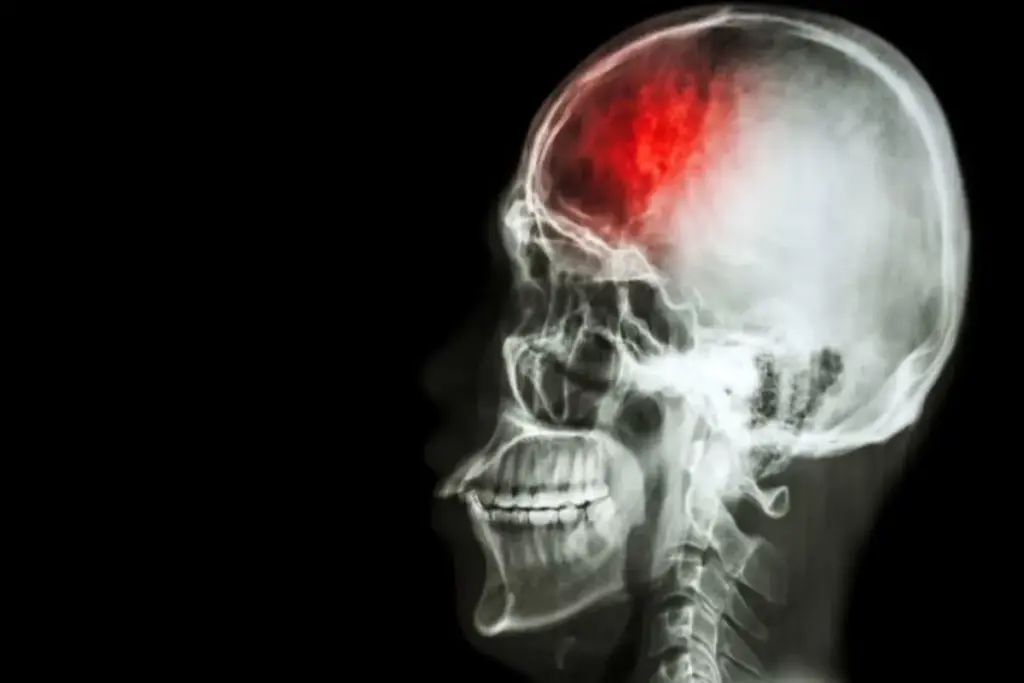

Neurosurgery is a highly intricate and delicate procedure. It carries significant risks and potential complications. Nearly 1 in 5 patients undergoing brain surgery may face adverse effects. These can range from infection and bleeding to neurological damage.

Exploring the intricacies of neurosurgical procedures reveals the importance of understanding risks. This includes craniotomy and cerebral tumor surgery. It’s vital for both patients and healthcare providers to grasp these risks.

It’s important for patients to know about neurosurgical procedures before brain surgery. Neurosurgery deals with surgeries for brain and nervous system issues.

These procedures include brain tumor surgery, aneurysm clipping, and epilepsy surgery. Each needs careful planning and execution.